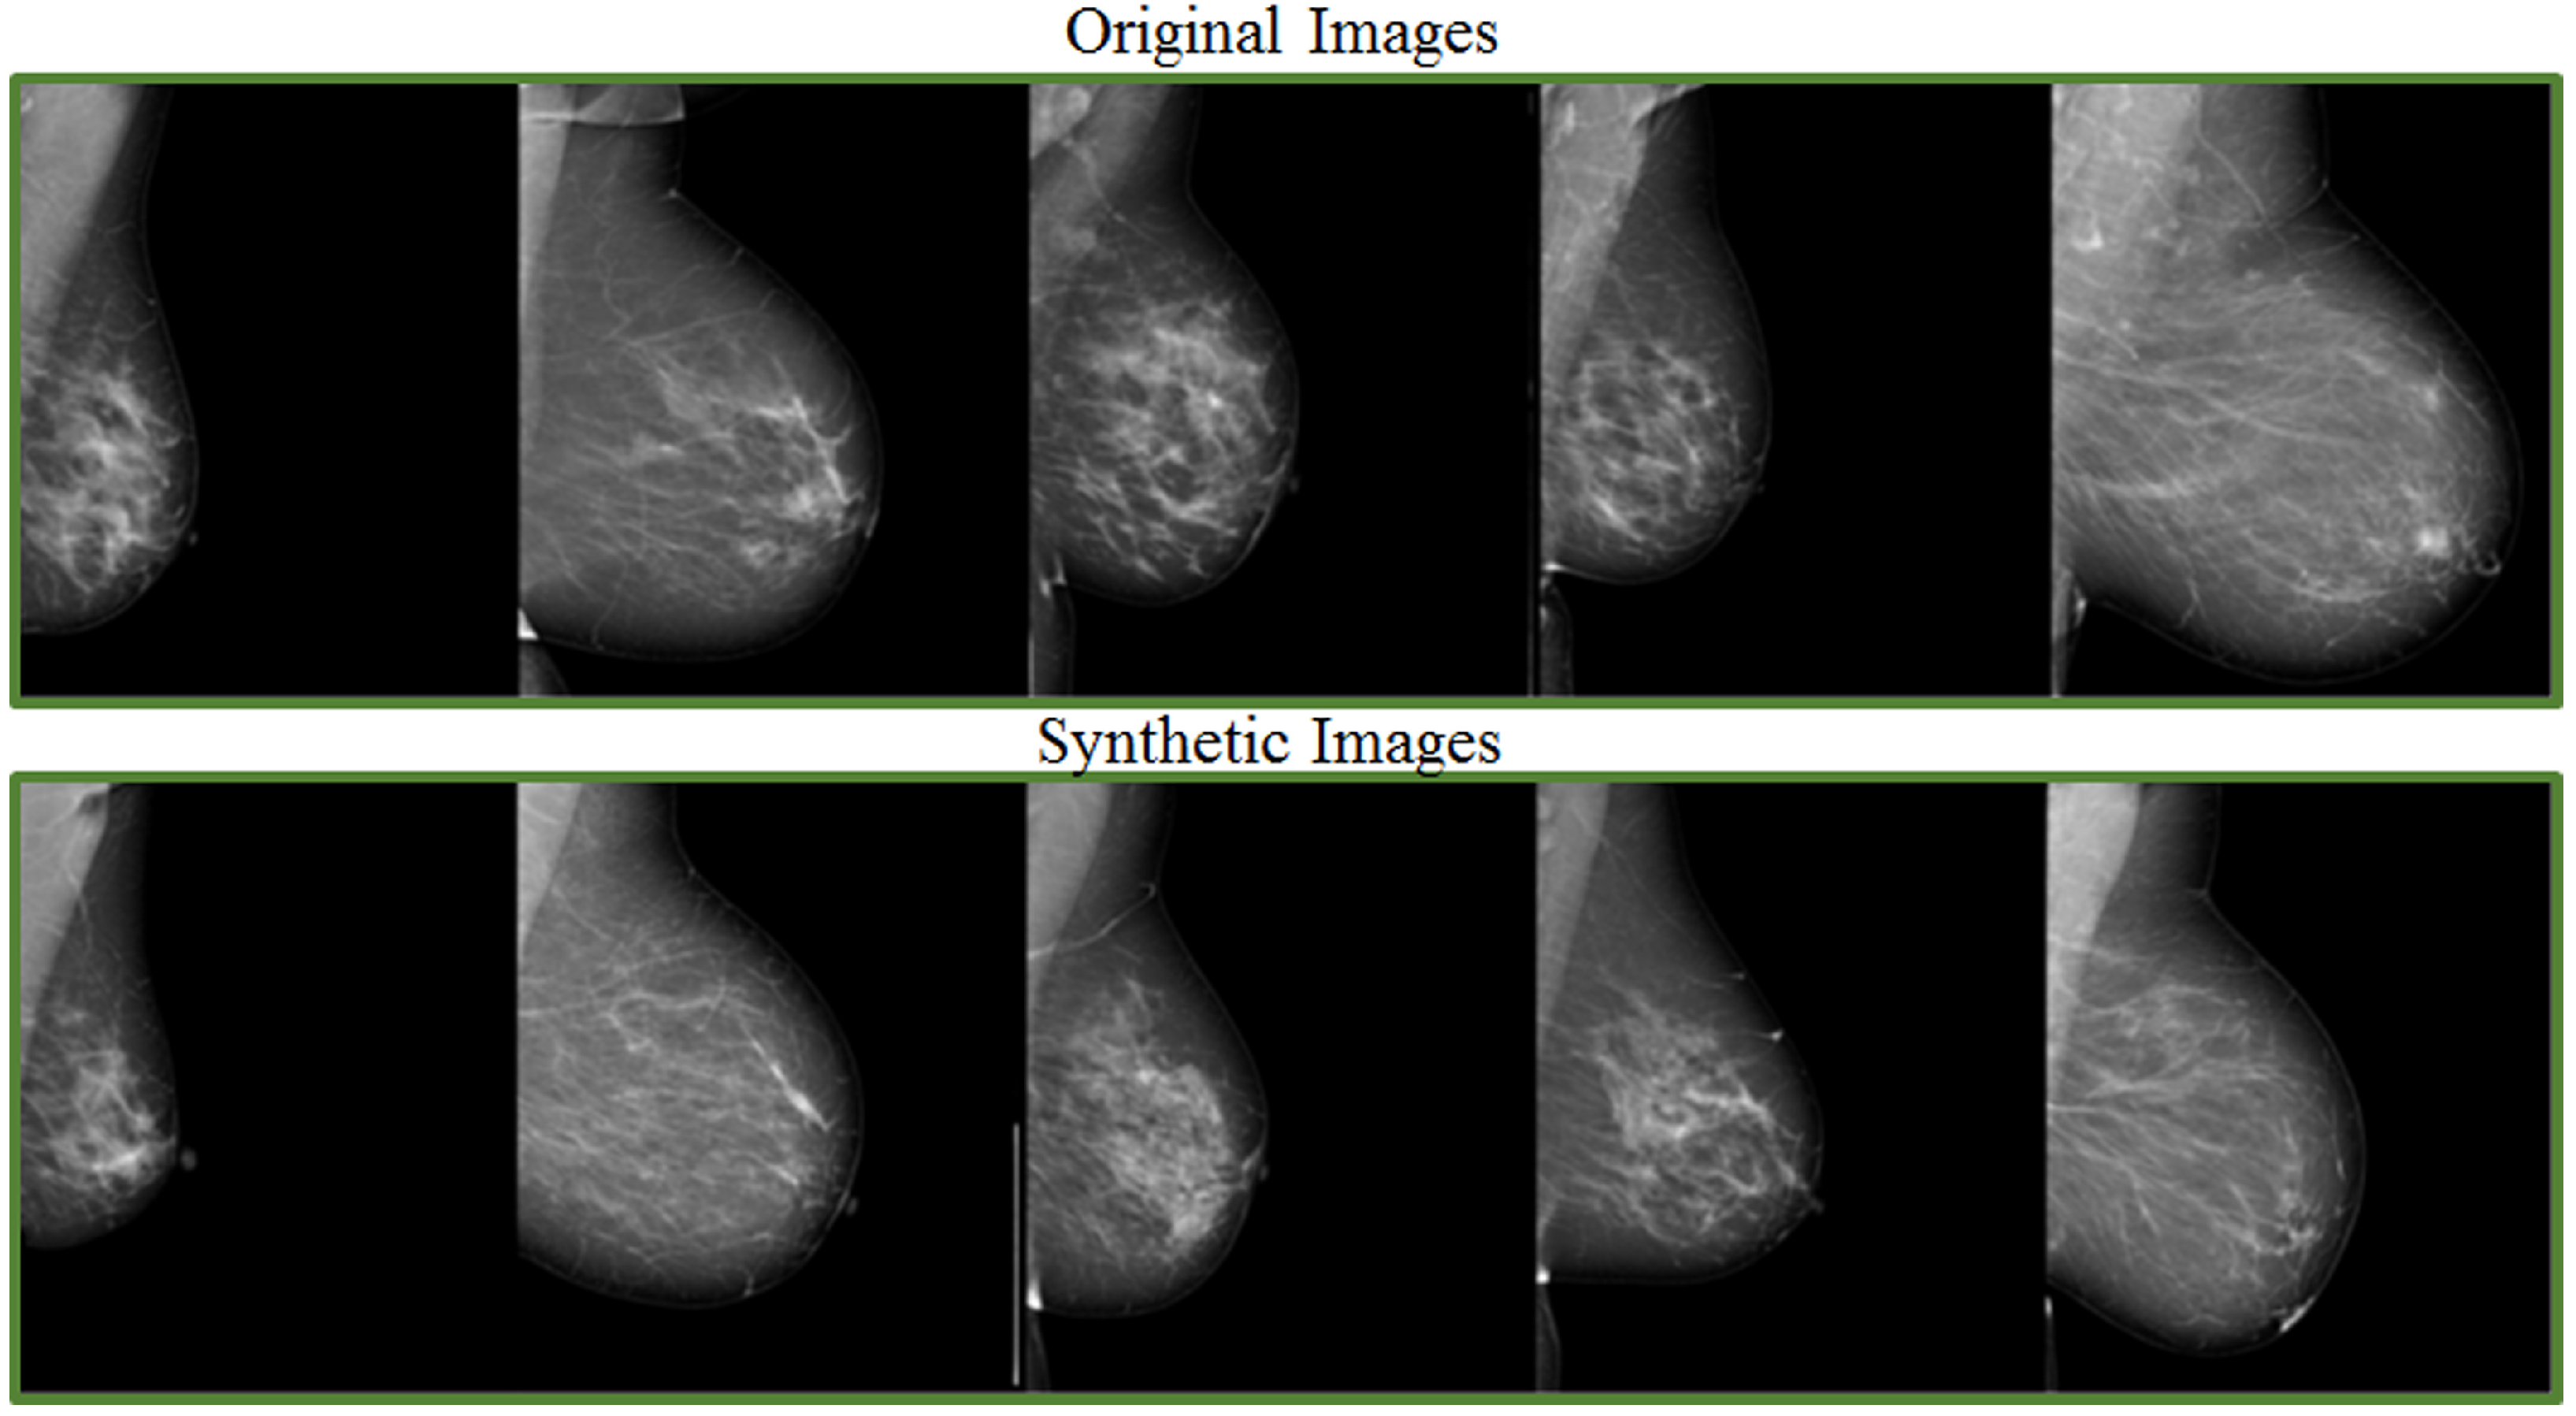

- Muramatsu, C.; Nishio, M.; Goto, T.; Oiwa, M.; Morita, T.; Yakami, M.; Kubo, T.; Togashi, K.; Fujita, H. Improving breast mass classification by shared data with domain transformation using a generative adversarial network. Comput. Biol. Med. 2020, 119, 103698. [Google Scholar] [CrossRef]

- Korkinof, D.; Heindl, A.; Rijken, T.; Harvey, H.; Glocker, B. MammoGAN: High-resolution synthesis of realistic mammograms. In Proceedings of the International Conference on Medical Imaging with Deep Learning–Extended Abstract Track, London, UK, 8–10 July 2019. [Google Scholar]